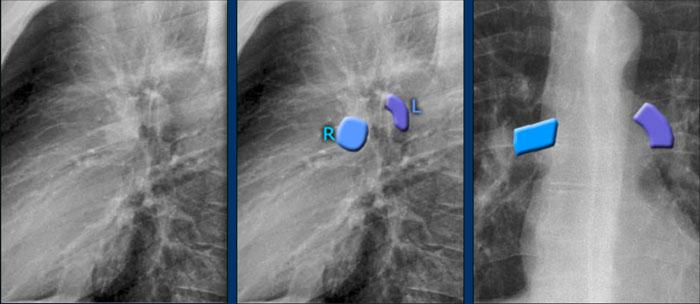

Mạch máu Phổi và Cấu trúc Rốn phổi

Động mạch phổi trái (màu tím) vòng cung phía trên phế quản gốc trái và nằm cao hơn động mạch phổi phải (màu xanh lam), động mạch này đi phía trước phế quản gốc phải.

Hiểu biết về giải phẫu rốn phổi bình thường trên tư thế nghiêng giúp phát hiện các bất thường.

Ví dụ:

- Trên tư thế PA, có thể nhận thấy rốn phổi to, nhưng khó phân biệt giữa giãn mạch máu và hạch to.

- Trên tư thế nghiêng, sự hiện diện của các đám mờ tròn ở những vùng mà mạch máu phổi bình thường không có mặt gợi ý mạnh mẽ đến hạch bạch huyết to.

Trong trường hợp này, bệnh nhân được chẩn đoán sarcoidosis.

Ngoài ra, lưu ý dải cạnh khí quản dày, một dấu hiệu khác của hạch to trung thất.

Một đặc điểm giải phẫu quan trọng cần lưu ý là rốn phổi trái bình thường nằm cao hơn rốn phổi phải.

Mối tương quan này xuất phát từ đường đi của các động mạch phổi: động mạch phổi trái vòng cung qua phía trên phế quản gốc trái, trong khi động mạch phổi phải đi phía trước phế quản gốc phải — vốn thường nằm thấp hơn phế quản gốc trái.

Trong một số ít trường hợp, hai rốn phổi có thể nằm cùng mức, nhưng rốn phổi phải tuyệt đối không được nằm cao hơn rốn phổi trái.

Trong hình minh họa này, các động mạch phổi thùy dưới được tô màu xanh lam để biểu thị máu chưa được oxy hóa.

Các động mạch này có hướng đi thẳng đứng hơn so với các tĩnh mạch phổi, vốn chạy theo hướng nằm ngang hơn về phía nhĩ trái — nằm ở phía dưới so với mức các động mạch phổi chính.

Trên phim X-quang ngực tư thế nghiêng, cả động mạch và tĩnh mạch phổi đều có thể nhận diện được và không nên nhầm lẫn với hình ảnh hạch bạch huyết to. Đôi khi, các tĩnh mạch phổi có thể trông nổi bật hơn bình thường.

Động mạch phổi chính trái đi phía trên phế quản gốc trái và nằm cao hơn động mạch phổi phải — vốn đi phía trước phế quản gốc phải.

Các hình ảnh đính kèm là tái tạo CT lát cắt dày theo mặt phẳng sagittal của lồng ngực, giúp tăng cường khả năng hiển thị các cấu trúc rốn phổi.

Các động mạch phổi thùy dưới đi xuống từ rốn phổi theo hướng thẳng đứng.